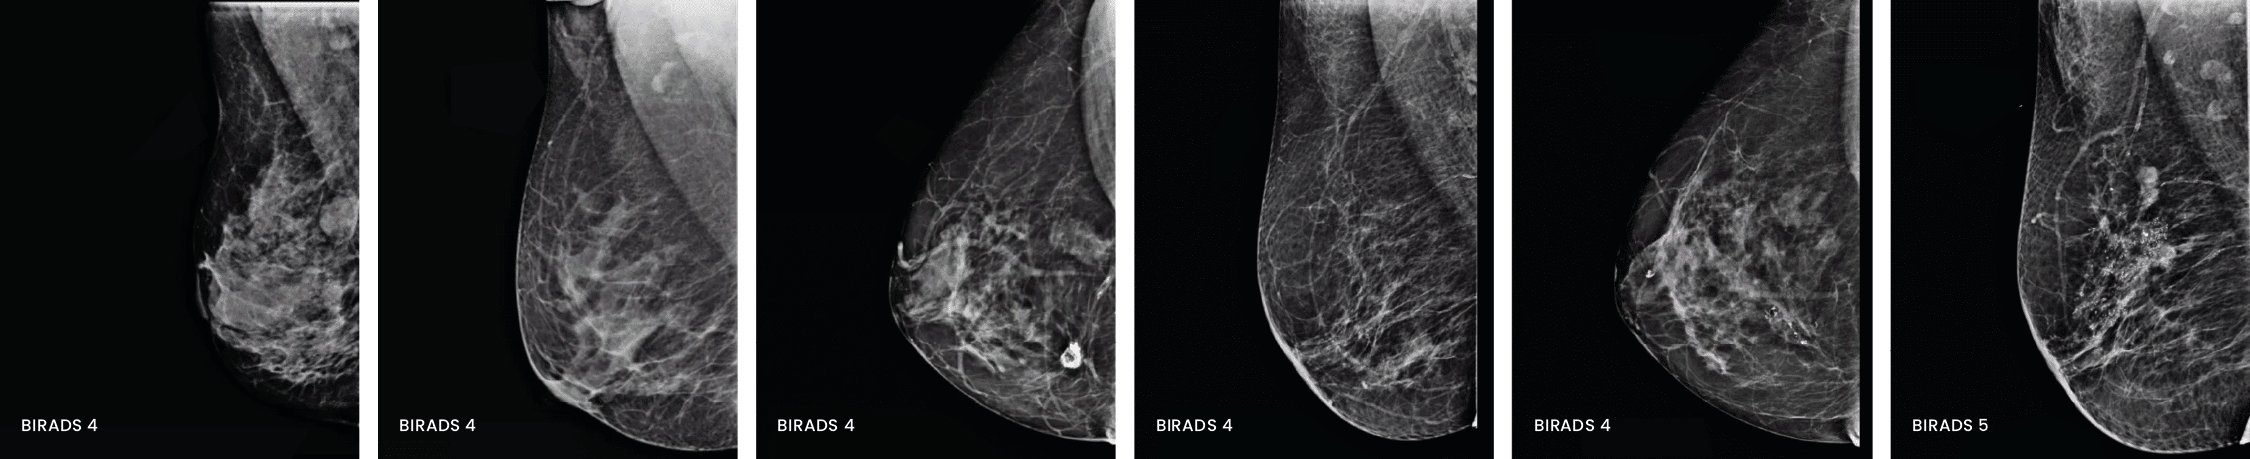

¿Qué es el BI-RADS y por qué aparece en tu informe?

BI-RADS es un sistema internacional que usan los médicos para clasificar los hallazgos de la mamografía o ecografía. Todos los informes terminan con un número del 0 al 6, que indica qué tan claro o preocupante es lo que se observó.

- BI-RADS 4 | Sospecha de anormalidad. Puede ser cáncer, por lo que se recomienda biopsia.

- 4A baja probabilidad (2–10%)

- 4B probabilidad moderada (10–50%)

- 4C alta probabilidad (50–95%)

- BI-RADS 5 | Alta sospecha de cáncer. Muy probable que sea cáncer (más del 95%). Se debe realizar biopsia.